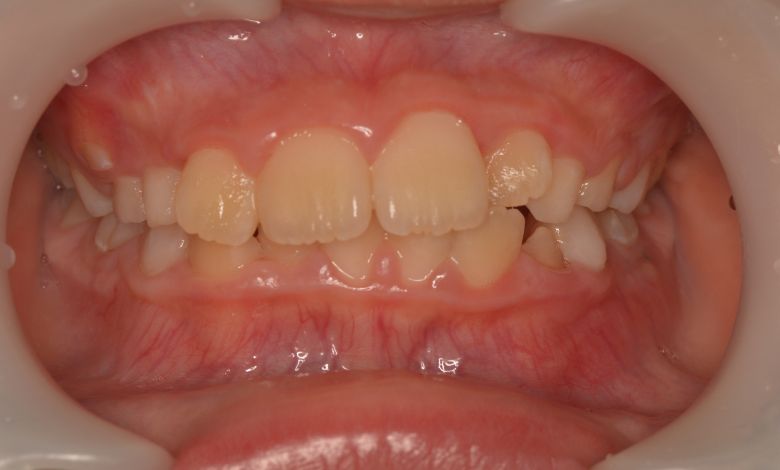

上下顎ともに犬歯が唇側に大きく突出しており、歯列弓が狭小なため、

他院では上下左右4本の便宜抜歯を前提とした矯正治療を提案されていました。

上顎には左右の犬歯が著しく唇側に偏位している

上下ともに歯並びが乱れており、噛み合わせにも大きな不調和が見られる